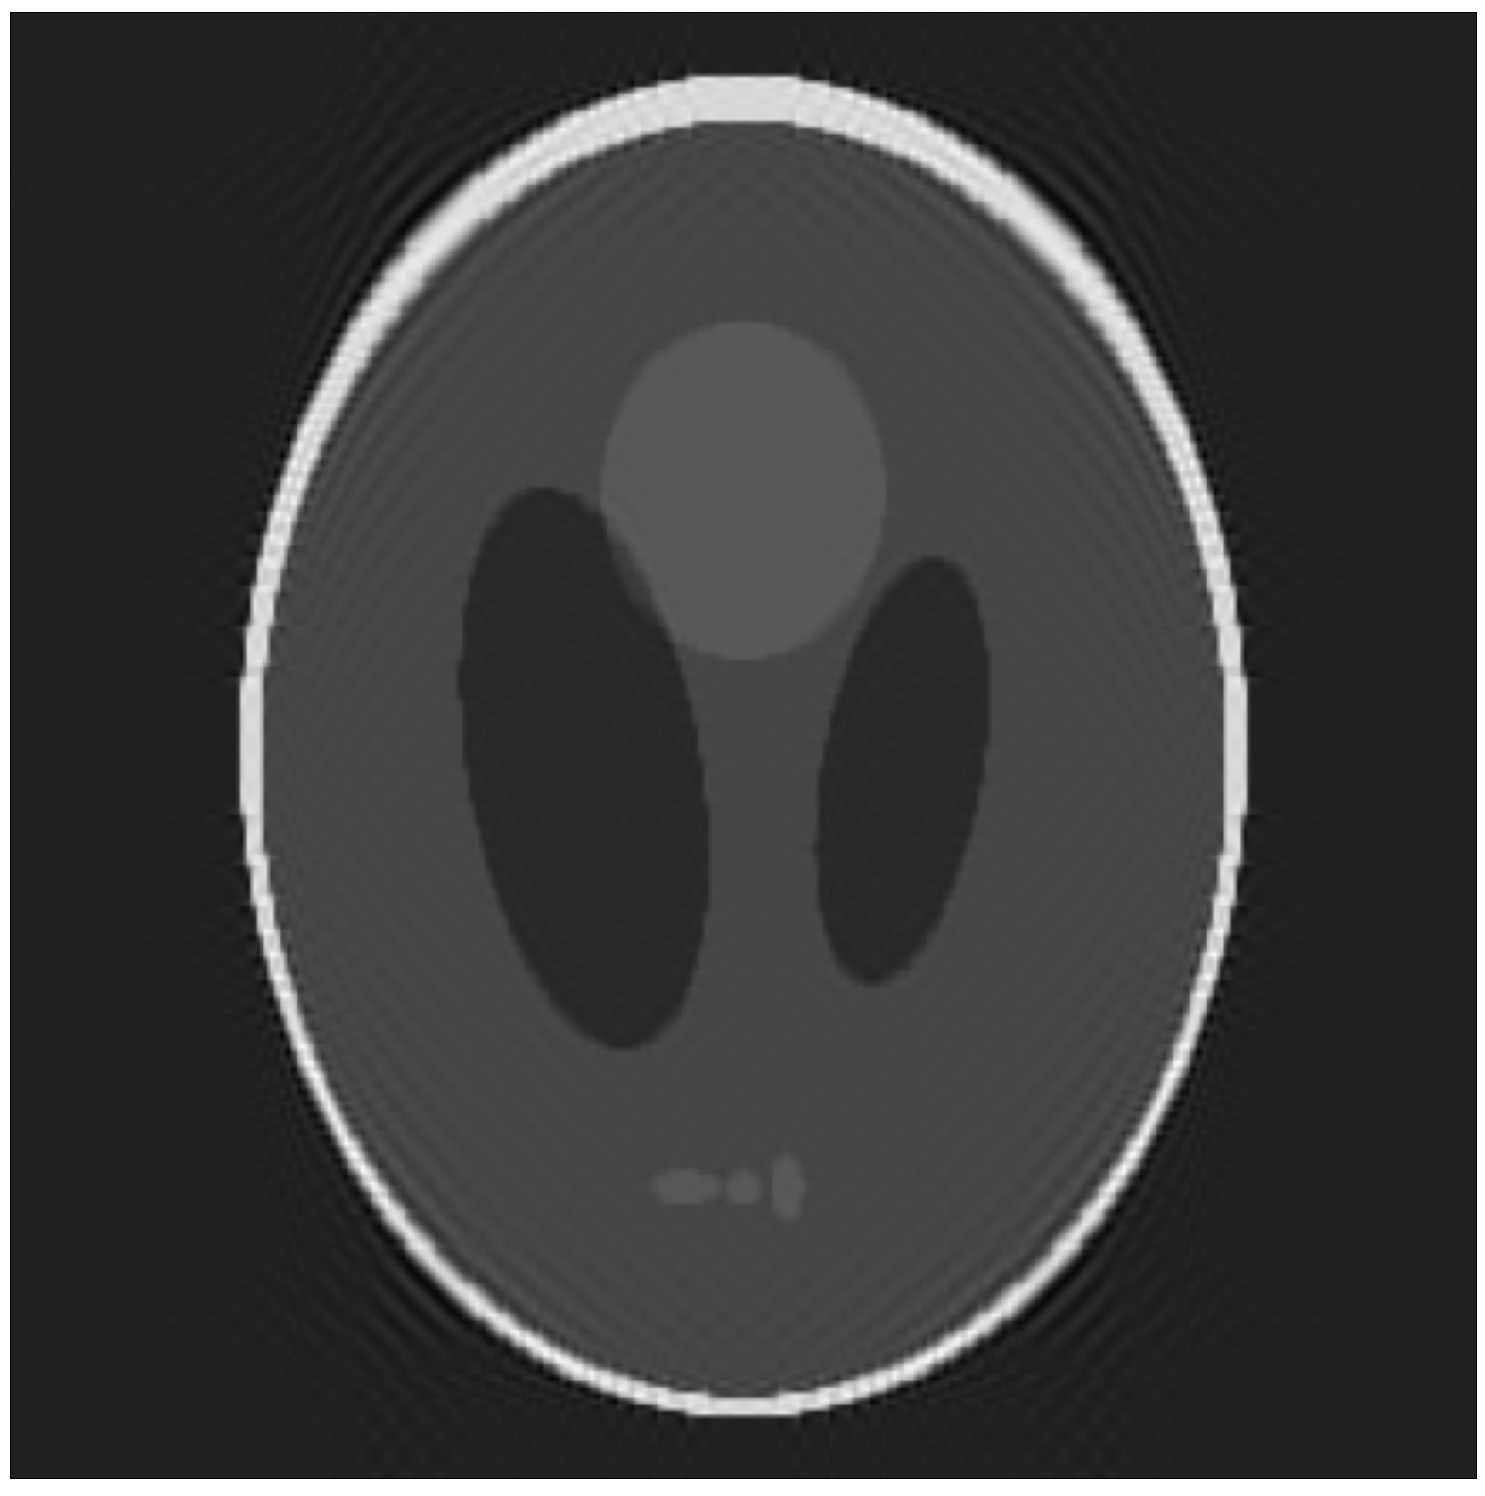

- The 3D Shepp–Logan (SL) phantom [26], a picewise-constant function made by the weighted sum of characteristic functions over different ellipsoids. The SL images were created in python with tomopy and nibabel [27] and saved in nifti format. The Segmention was made with a python script by grouping the voxels of the same intensity values. Size: ;